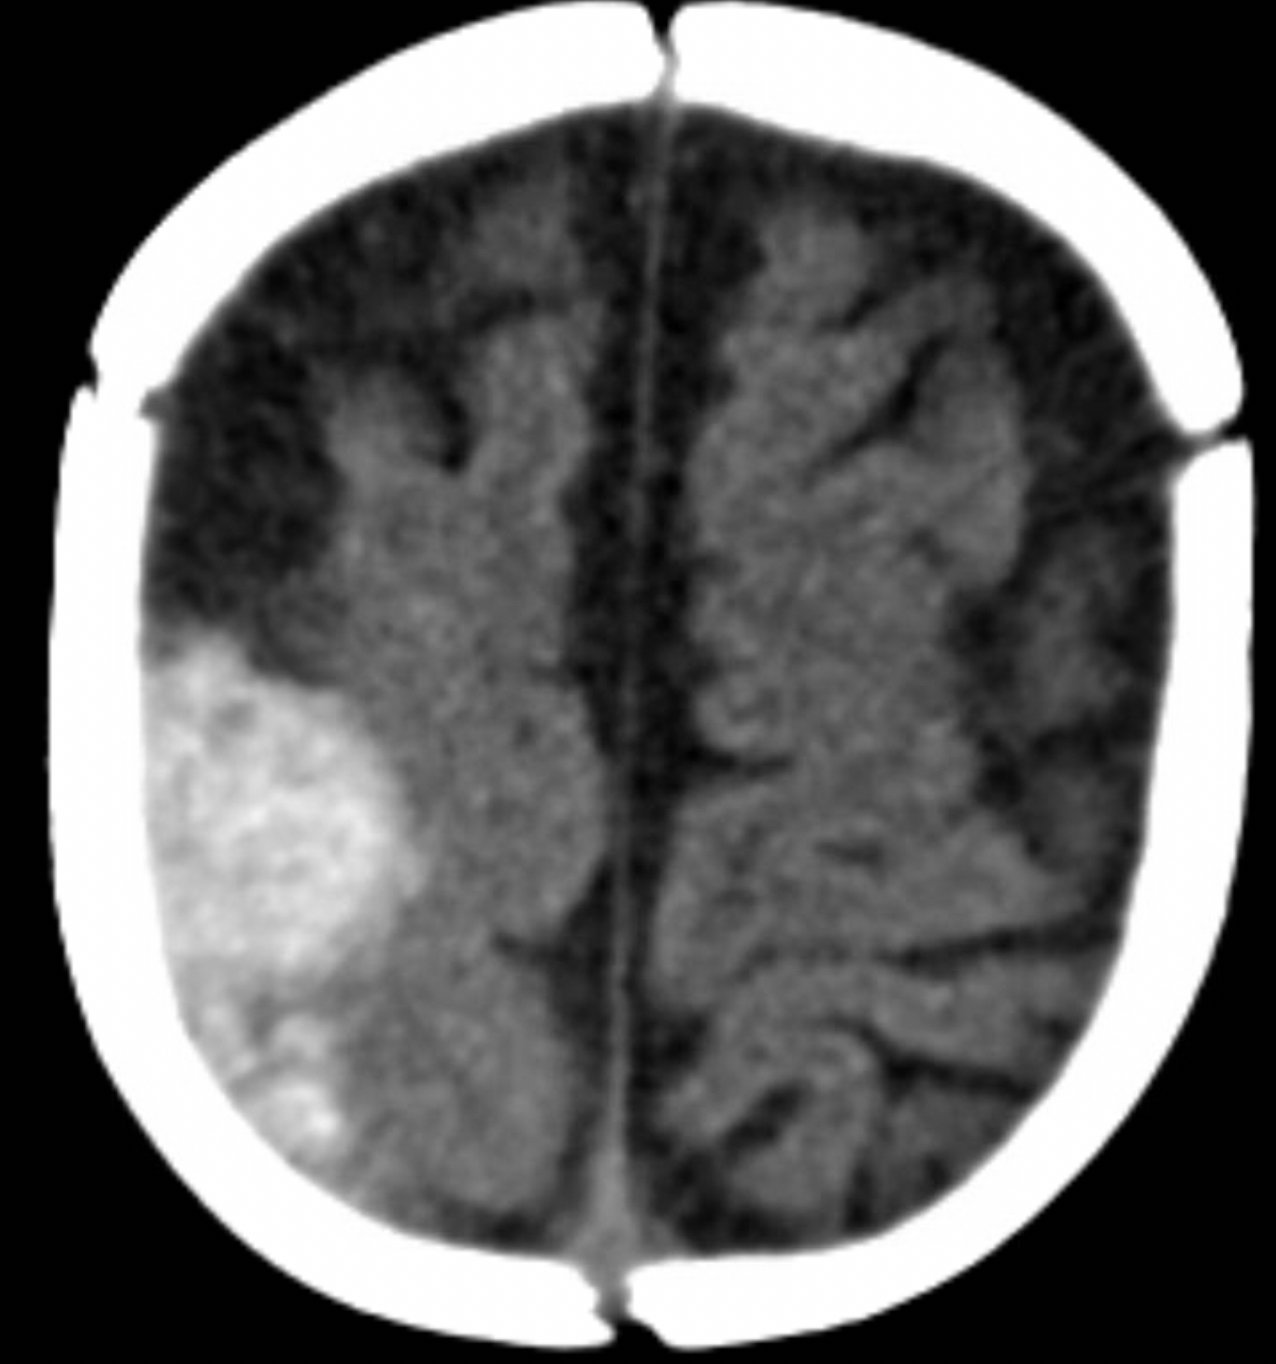

A computed tomography (CT) scan of the head without contrast was obtained out of concern for intracranial pathology due to the patient’s young age and the witnessed focal seizure. The CT showed a 4.2 x 1.2 x 1.5 cm acute extra-axial intracranial right frontoparietal hemorrhage favoring epidural over subdural hemorrhage given its lenticular shape. There was no underlying fracture, herniation or midline shift identified.

Given the concern for non-accidental trauma in this nonmobile child with no history of trauma, pediatric surgery and neurosurgery were consulted and further bloodwork was obtained, revealing elevated partial thromboplastin time (PTT) and a normal prothrombin time (PT). Further work-up led to a diagnosis of severe hemophilia A. He was managed non-operatively with factor VIII infusions to achieve normal factor levels. He remained neurologically stable without further seizure activity during his hospitalization. A skeletal survey showed no fractures. He received levetiracetam for 6 months and had no neurological deficits.